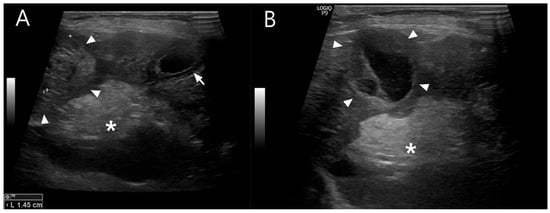

At the two-week postoperative follow-up, no surgical complications were noted. Subsequent rechecks were spaced at monthly intervals. Four months postoperatively, serum biochemistry showed normal hepatic enzyme levels, and radiographs demonstrated increased liver size compared to preoperative imaging (Figure 6). The patient was receiving levetiracetam (5–10 mg/kg PO BID), ursodeoxycholic acid (10 mg/kg PO BID), and silymarin (10 mg/kg PO BID), with plans for gradual tapering.

Figure 6.

Radiographic liver size evaluation using the liver-to-T11 vertebral length ratio (right lateral view). Measurements were taken from the ventral border of the caudal vena cava to the caudoventral liver apex (liver length), and the midpoint of T11 (vertebral length). Black lines indicate the measured liver length and the T11 vertebral length used to calculate the liver-to-T11 ratio. (A) Preoperative ratio: 4.13. (B) One month postoperatively: 4.52. (C) Four months postoperatively: 4.90, suggesting progressive hepatic enlargement following extrahepatic portosystemic shunt (EHPSS) attenuation.